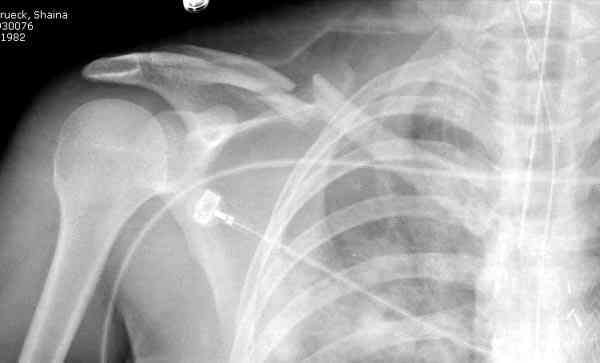

Второй случай тоже недавно оперирован по поводу

ложного сустава, в марте травма, через 4.5 половиной

операция..